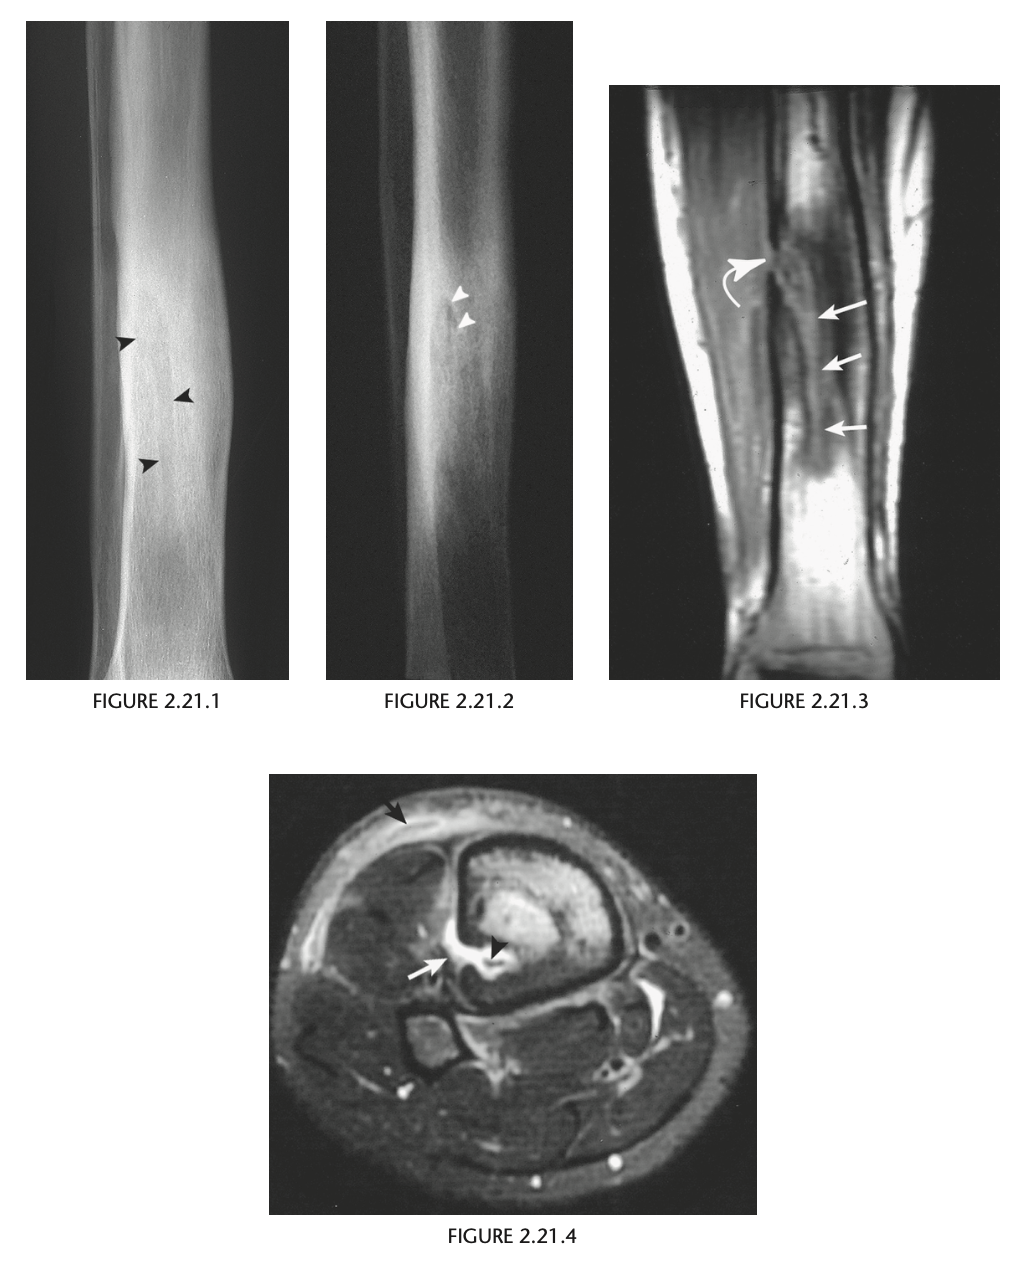

A 21-year-old man with a prior puncture wound to the leg

Radiographs of the right tibia and fib-

ula (Figs. 2.21.1 and 2.21.2) show a vague, irregu-

lar linear radiolucency within an area of sclerosis

in the distal third of the tibia (arrowheads). Coronal

T1-weighted MRI of the tibia reveals a serpiginous

region of decreased marrow signal extending over

several centimeters (Fig. 2.21.3, arrows) and a de-

fect in the lateral tibial cortex (curved arrow). Axial

T2-weighted MRI through the same region demon-

strates a bony sequestrum (Fig. 2.21.4, arrowhead)

and increased signal intensity (i.e., marrow edema)

within the tibia. A sinus tract extends through the

lateral aspect of the posterior tibia (white arrow) to

the skin surface anteriorly (black arrow), with edem-

atous changes in the subcutaneous tissues.

Chronic osteomyelitis with a draining

sinus tract

In acute

osteomyelitis, the earliest radiographic sign is ob-

scuration of the normal fat planes as a result of soft-

tissue swelling. Bony changes usually do not appear

until 1 to 2 weeks after the onset of the infection.

Osteomyelitis typically affects the epiphysis in in-

fants and adults and the metaphysis in children and

is multifocal in neonates. The MRI features of acute

osteomyelitis include areas of diminished signal in-

tensity on short TE images within the normally high.

signal intensity of the fatty bone marrow. Long TE

images with fat-suppression or inversion-recovery

images usually show areas of increased signal inten-

sity in muscle, cortical bone, and periosteum that

are not well demonstrated on short TE sequences.

T1-weighted fat-suppressed, gadolinium-enhanced

images increase sensitivity and specificity in the di-

agnosis of infection.

The radio-

graphic findings of chronic osteomyelitis include

prominent cortical thickening and a mixed pattern

of osteosclerosis and osteolysis. Signs suggesting re-

activation of infection include the development of

new, ill-defined areas of osteolysis; thin, linear peri-

ostitis; or the presence of a sequestrum and draining

sinus tract.

An unusual complication of a long-standing

draining sinus tract in chronic osteomyelitis is squa-

mous cell carcinoma.